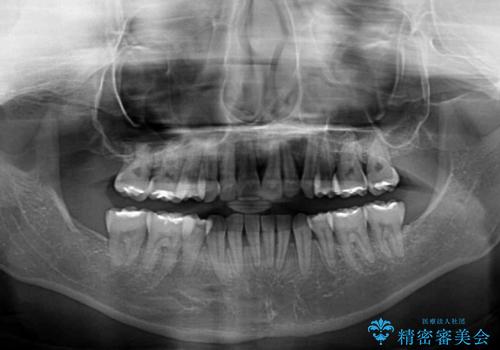

アンカースクリューを用いて正中位置を調整したことで、上下の正中位置をほぼ一致させることができました。

移動量が多かったため、治療期間は長くなりましたが、大変満足のいく仕上がりとなりました。